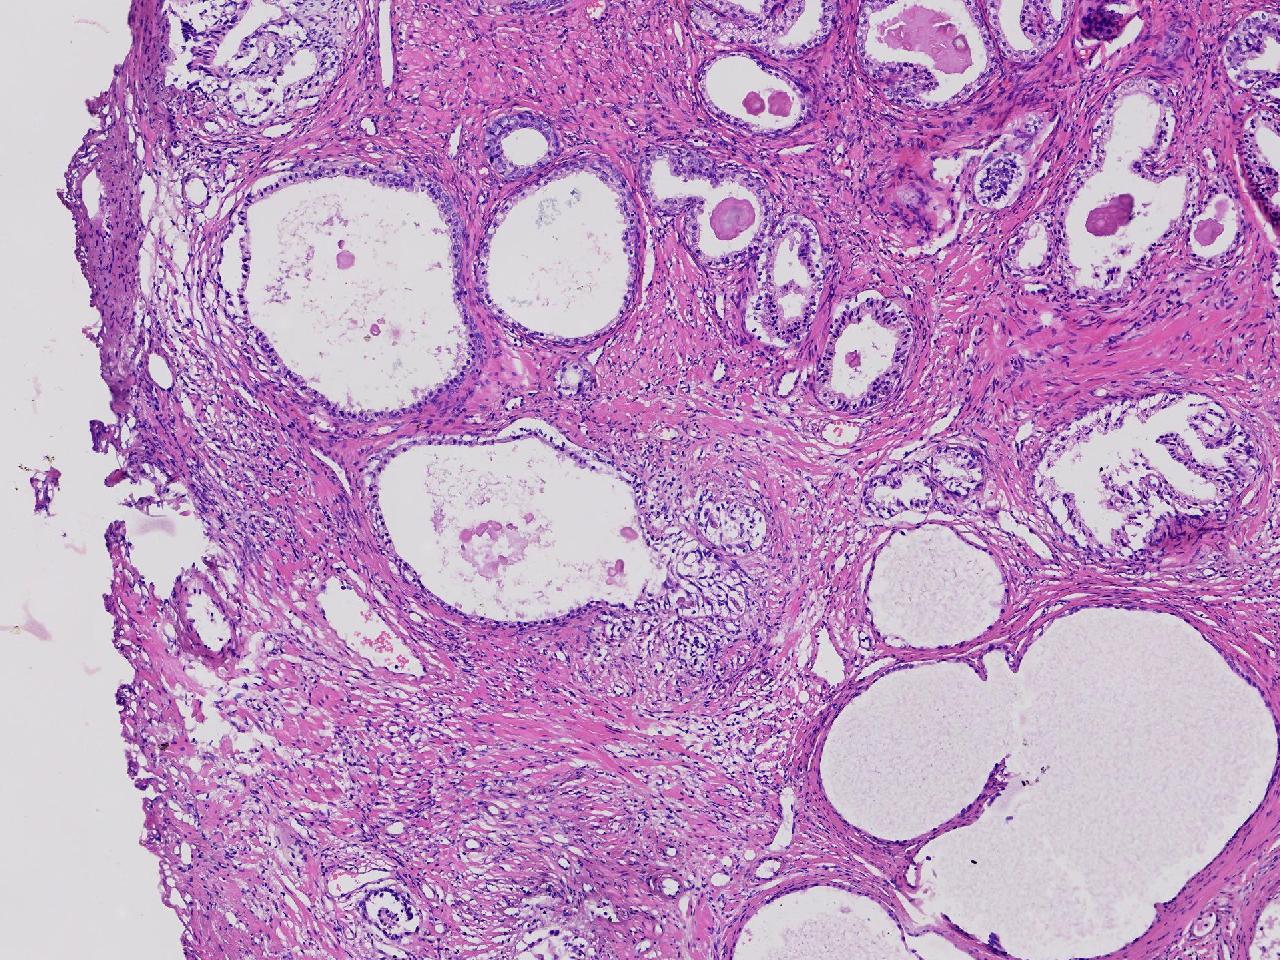

良性前列腺增生吧?

性别

男

年龄

65岁

临床诊断

前列腺电切组织

一般病史

进行性排尿困难半年余。

标本名称

前列腺

大体所见

图2

、良性前列腺增生

BPH.